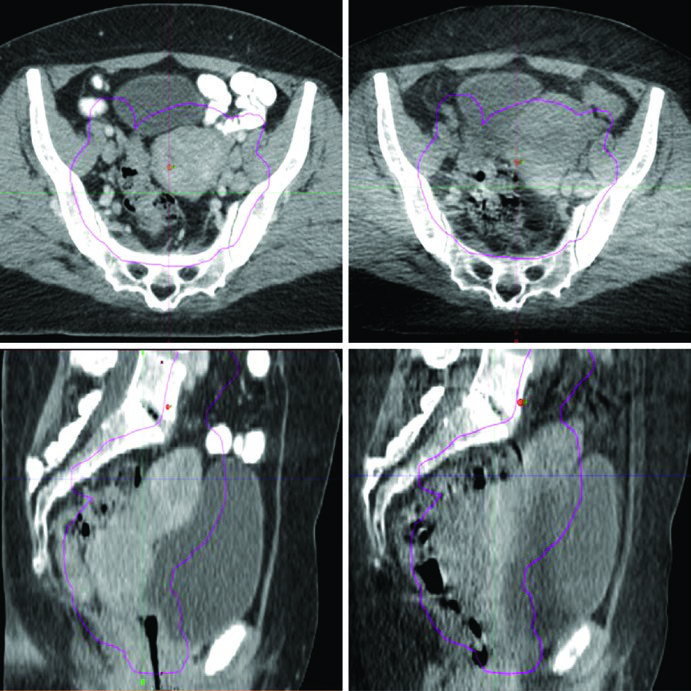

O replanejamento adaptativo divide-se em três categorias principais: offline (entre frações), online (imediatamente antes de uma fração) e em tempo real (durante a entrega). Cada uma responde a cenários clínicos diferentes, e a escolha depende da infraestrutura disponível e do grau de variação anatômica esperado.

Plano-do-dia (plan-of-the-day): gera uma biblioteca de planos paciente-específicos correspondendo a diferentes volumes-alvo e configurações de movimentação orgânica. Antes de cada fração, o CBCT seleciona o plano mais similar à configuração do dia. Essa estratégia é elegante porque não exige replanejamento em tempo real, mas demanda investimento inicial na criação da biblioteca.

Replanejamento programado: pode ser feito com RM semanal. Registro deformável de imagem modela a dose acumulada nos alvos e OARs. Na prática, funciona bem para pacientes que perdem peso progressivamente ou cujos tumores regridem significativamente durante o tratamento.

A radioterapia adaptativa offline deve ser considerada para pacientes com perda de peso significativa ou mudança substancial no tamanho tumoral. Uma nova simulação pode ser necessária se o replanejamento não puder ser realizado com as imagens adquiridas na sala de tratamento. Sistemas avançados de planejamento permitem monitoramento automatizado de dose e métricas dose-volume que podem ser revisadas offline para orientar a decisão de replanificar.

Na radioterapia adaptativa online, a variação no enchimento do reto e da bexiga desloca tanto os alvos quanto os OARs de maneiras que a simulação CT inicial não captura. Tecnologias emergentes integram CBCT iterativo para cálculo de dose e replanejamento diário, ou utilizam RM para replanejamento online. A plataforma MR-Linac representa o exemplo mais avançado dessa categoria, combinando imagem em tempo real com adaptação do plano na mesma sessão.